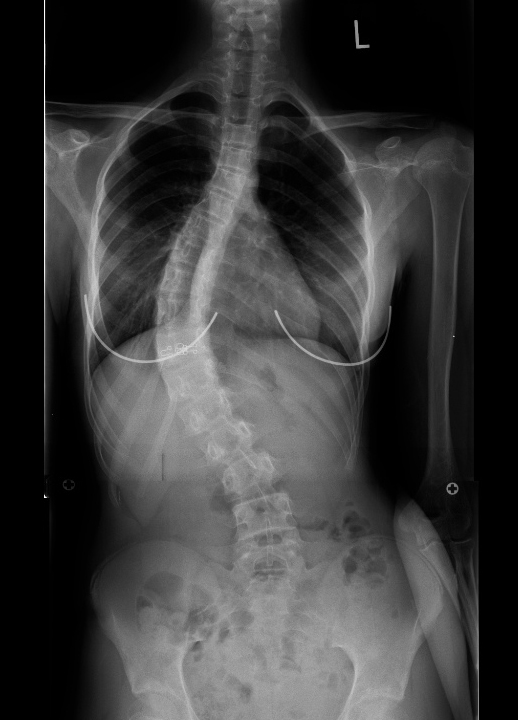

| Pre-op | Post-op |